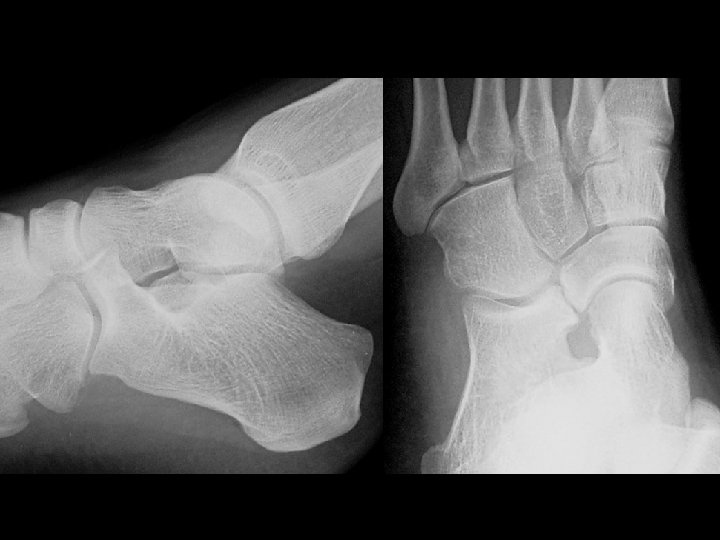

Homolateral Lisfranc fracture-dislocation • Findings: – Lateral dislocation of 1 st thru 5 th metatarsals at the Lisfranc joints – types • divergent • homolateral • partial incongruity • ddx: – NONE! – This is an Aunt Minnie!

Diabetic Charcot foot & Lisfranc fracture dislocations • Findings: – Destruction, debris, dislocation, and increased density of Lisfranc joints – Pes planus – Vascular calcifications indicative of DM • ddx: – osteomyelitis